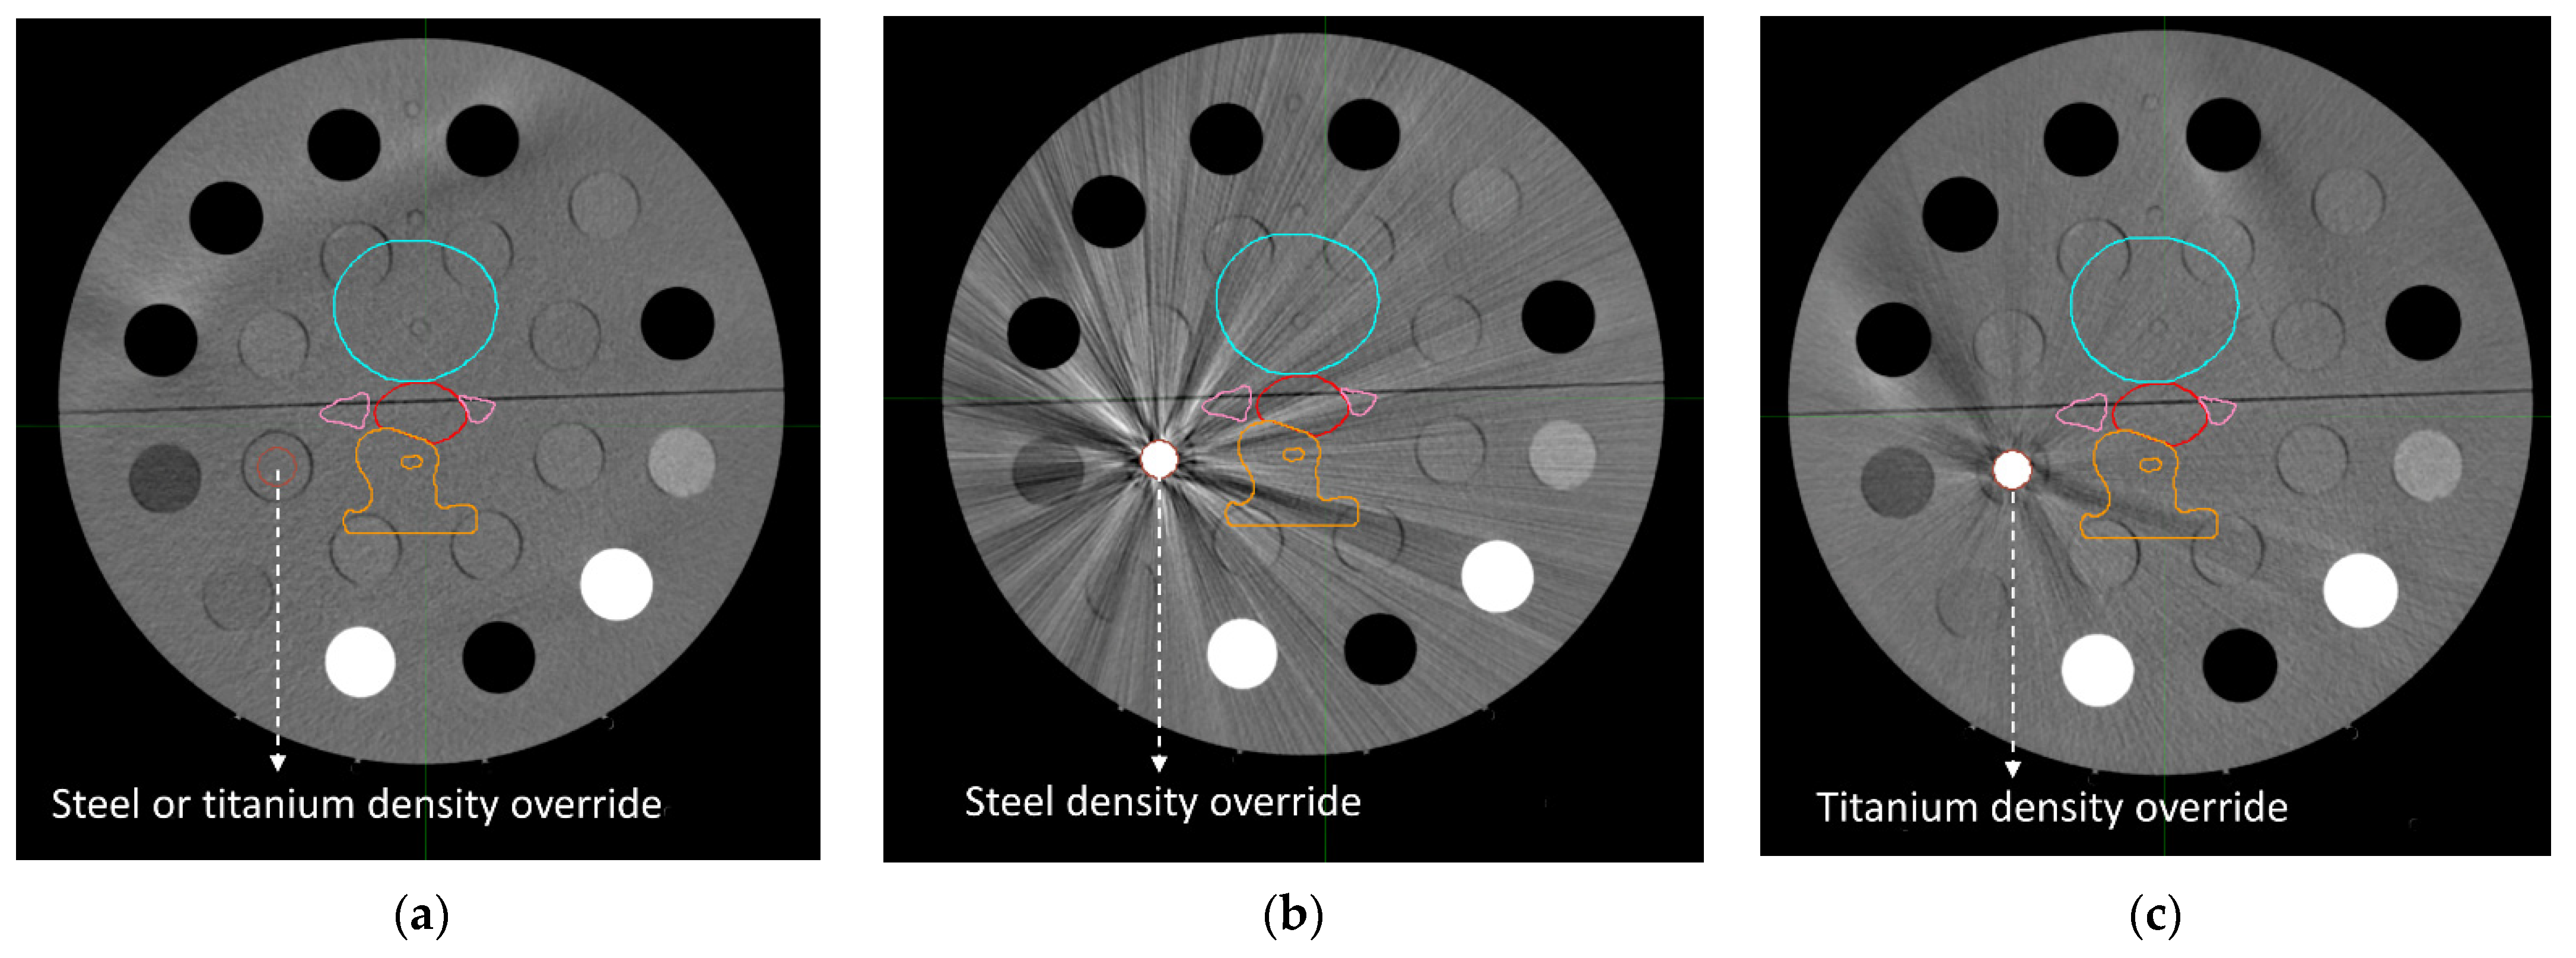

2.4. Dose Distributions

3.3. Dose Distributions